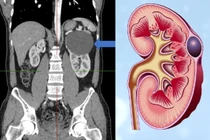

Thận bình thường và thận đa nang - BVCC

TS.BS Nghiêm Trung Dũng, Giám đốc Trung tâm Thận tiết niệu và Lọc máu, Bệnh viện Bạch Mai cho biết, nang thận có hai loại: di truyền và mắc phải. Nang thận di truyền, thường gọi là thận đa nang, biểu hiện đặc trưng xuất hiện nang thận ở cả 2 bên với kích thước khác nhau như chùm nho.